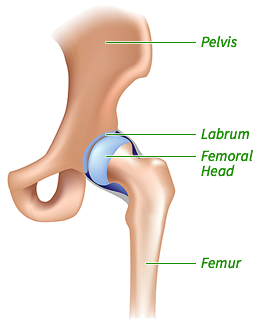

Hip arthroscopy involves several small incisions around the hip that allow a small camera and instruments access to the hip joint. This minimally invasive procedure allows for outpatient surgery, very little scarring, faster recovery, prompt rehabilitation, and a quicker return to activities. This animation from the Hospital for Special Surgery is a great overview of hip arthroscopy.